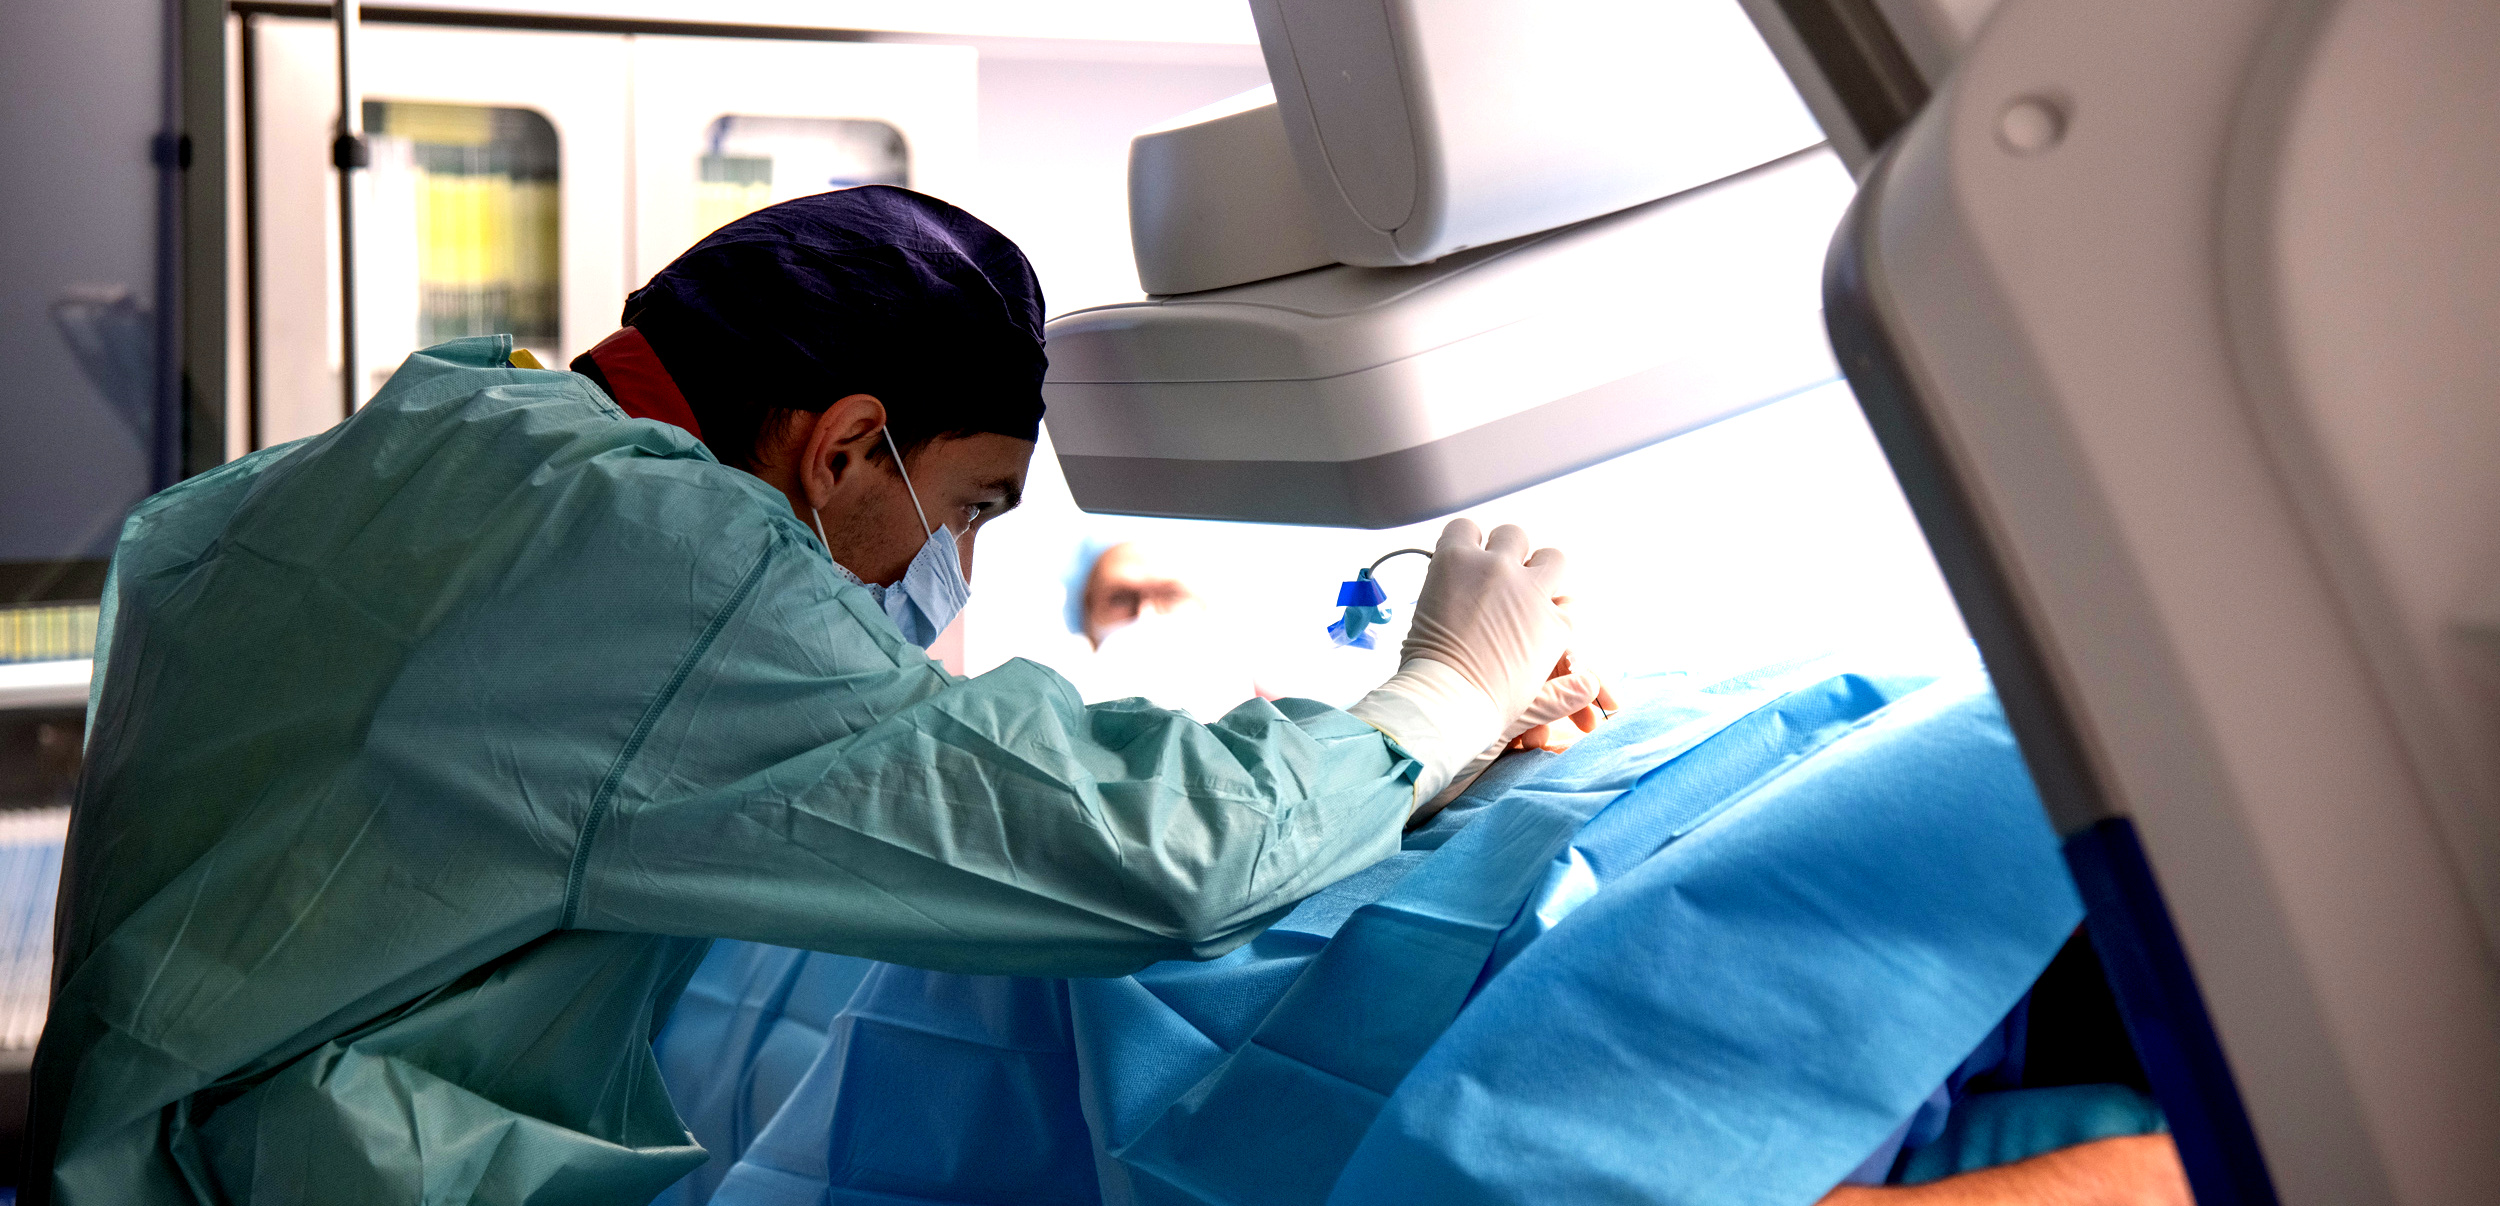

Lekarze z oddziału neurochirurgicznego Wojewódzkiego Szpitala Specjalistycznego w Słupsku zaczynają przeprowadzać zabiegi termolezji, czyli leczenia bólu za pomocą wysokiej temperatury. Z tych zabiegów może skorzystać nawet kilkuset pacjentów rocznie.

– Na przykład mamy pacjenta z bólem tak zwanym rzekomokorzeniowym. Nie ma dyskopatii, natomiast bardzo go bolą plecy. Z czego może wynikać ten ból? Z przeciążenia stawów międzykręgowych. Co możemy wtedy zrobić? Zniszczyć unerwienie tych stawów. Robimy to, wbijając igłę pod kontrolą prześwietlenia rentgenowskiego, bo jest to metoda wymagająca precyzji. Do igły wprowadzamy emiter prądów wysokiej częstotliwości i nagrzewamy tkanki do temperatury – w tym konkretnym przypadku – 85 stopni Celsjusza. Nagrzewamy miejscowo tylko tę strukturę, która nas interesuje, bo pole rażenia tej elektrody jest niewielkie – mówi Rafał Muchowski, neurochirurg z Oddziału Neurochirurgii Wojewódzkiego Szpitala Specjalistycznego w Słupsku.

W słupskim szpitalu termolezje wykonywane są w ramach pobytów jednodniowych. Pacjent przychodzi do szpitala rano, przechodzi badania, a następnie wykonywany jest zabieg i po 2-3 godzinach odpoczynku wychodzi ze szpitala do domu. Taki sposób przeprowadzania zabiegów daje większa szansę uniknięcia powikłań.

Wysoki poziom wykonywania termolezji w słupskim szpitalu jest możliwy dzięki używanemu sprzętowi wysokiej klasy, np. nowoczesnemu angiografowi zakupionemu przez szpital na początku 2025 roku.